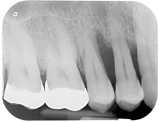

Ein gesundes Zahnfleisch sieht blass rosa aus und blutet nicht beim Zähneputzen. Bakterielle Beläge und Zahnstein führen zu einer Entzündung des Zahnfleisches (Ginigivitis). Eine Behandlung bei der Dentalhygienikerin kann diese Entzündung stoppen. Bleibt die Entzündung bestehen, entstehen Zahnfleischtaschen und der Zahnhalteapparat (Zement und Knochen) wird abgebaut. Die Zähne beginnen zu wackeln und können verloren gehen. Durch eine intensive Zusammenarbeit von Dentalhygenikerin und Zahnarzt (Parodontalbehandlung) kann dieser Prozess gestoppt werden und Knochen und Zement teilweise regenerieren, so dass die eigenen Zähne bis ins hohe Alter erhalten werden können.